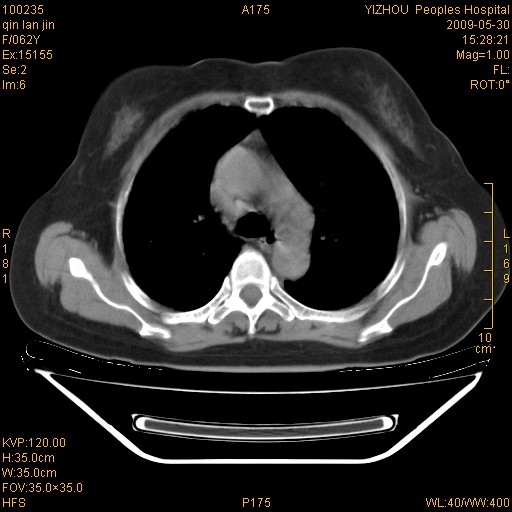

标题: CT20268:肺泡癌?间质性肺炎?

女,62岁,近二年经常咳嗽,近二个月,消瘦、乏力。

前面一张胸片是今天照的,后面一张胸片是去年9月份的。